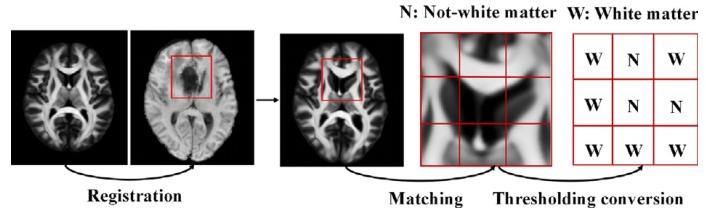

Fig. 1. The postoperative T1C MRI images after total resection of different patientsare shown in (a) and ©. The amplified areas of the blue bounding areas by 2.5 timesare shown in (b) and (d). Specifically, green and red curves are operative cavities andHRA of gliomas

图1 (a)和(c)展示了不同患者全切除术后的T1增强(T1C)MRI图像。(b)和(d)为蓝色框选区域的2.5倍放大图。其中,绿色曲线表示手术腔,红色曲线表示胶质瘤的高风险复发区域(HRA)。

Fig. 3. (a) Early postoperative image, where operative cavity was painted in red; (b)minimized rectangle that covered the ROI (the operative cavity combined with the1.5 cm margin) was used to crop the early postoperative image; and © rectangularROI was amplified and divided into 3 × 3 patches.

图3 (a)术后早期图像,其中手术腔用红色标注;(b)采用覆盖感兴趣区域(ROI,即手术腔联合1.5厘米边缘区域)的最小矩形对术后早期图像进行裁剪;(c)将矩形感兴趣区域放大并划分为3×3的图像块(patches)。

Fig. 5. Steps of constructing a weighted map

图5 加权图的构建步骤